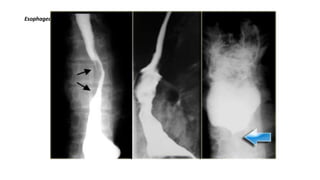

oesophageal web

• More commonly occur in the cervical esophagus near

cricopharyngeus muscle than in the thoracic esophagus. They

typically arise from the anterior wall and never from the posterior

wall; they can also be circumferential 4. Occasionally, multiple webs

are visualized during maximal distension.

Multiple smooth tapered concentric narrowing of the cervical esophagus in keeping with esophageal webs.

•More commonly occurin the cervical oesophagus near cricopharyngeus muscle than in the thoracic oesophagus. They •typically arise from the anterior wall and never from the posterior wall; they can also be circumferential. • Associations • Plummer-Vinson syndrome • GvHD • GORD/GERD (especially a distal oesophagus web) • external beam radiation. • Esophageal webs refer to an esophageal constriction caused by a thin mucosal membrane projecting into the lumen. oesophageal web

• More commonlyoccur in the cervical esophagus near cricopharyngeus muscle than in the thoracic esophagus. They typically arise from the anterior wall and never from the posterior wall; they can also be circumferential 4. Occasionally, multiple webs are visualized during maximal distension. • Associations • Plummer-Vinson syndrome • graft-versus-host disease • gastro-esophageal reflux disease (especially a distal esophagus web) 7 • external beam radiation

Multiple smooth taperedconcentric narrowing of the cervical esophagus in keeping with esophageal webs. • Plummer-Vinson syndrome with jet effect